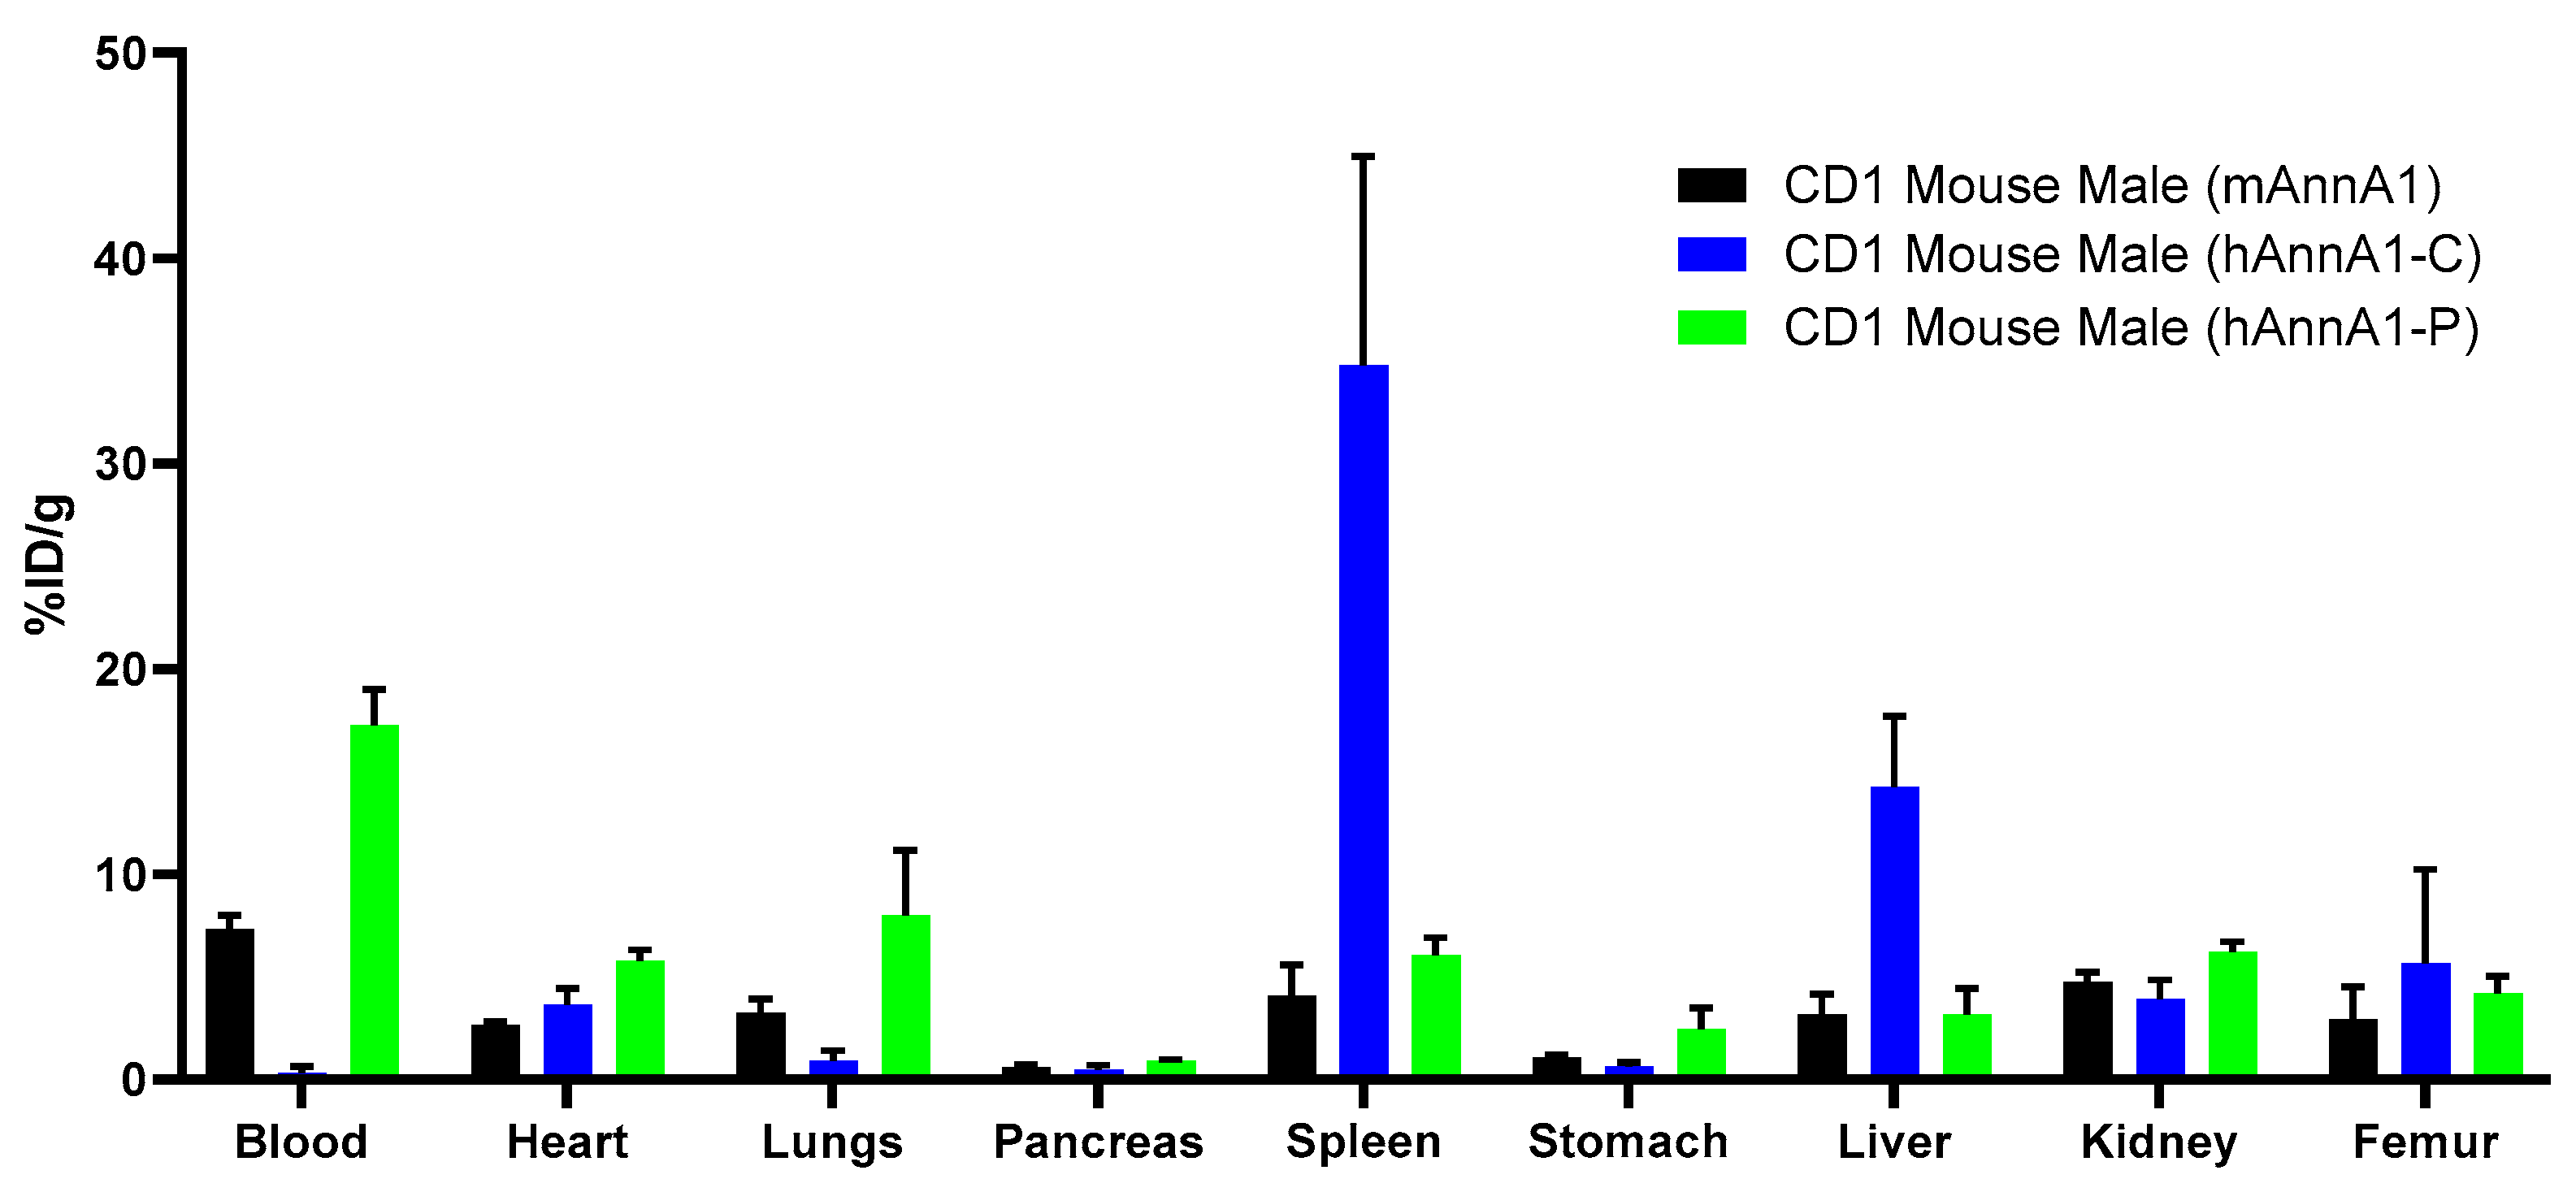

2. Results